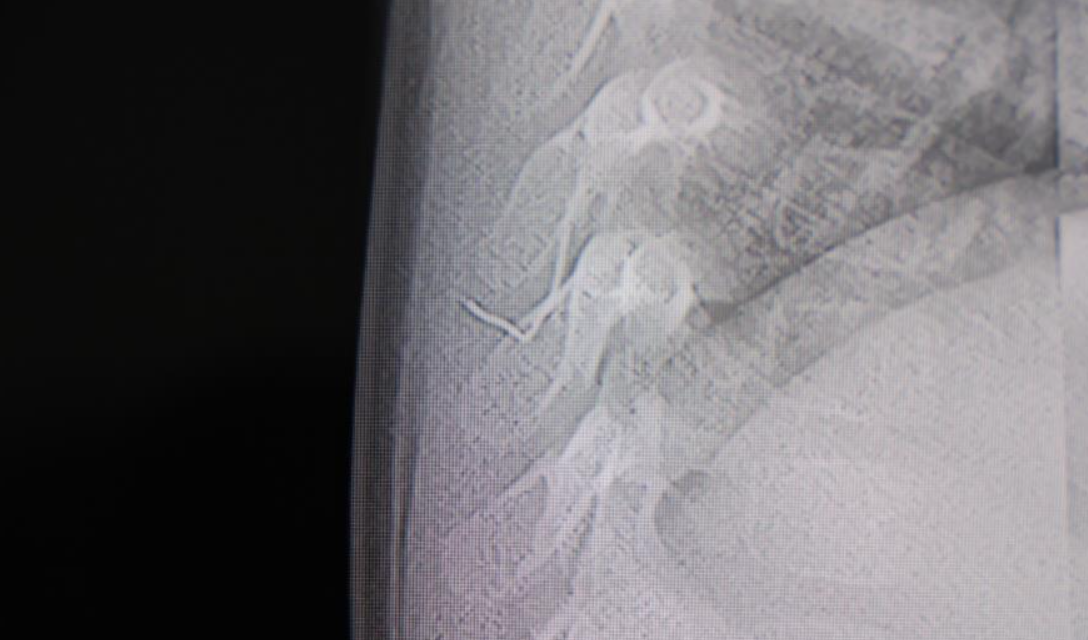

Alınan bilgiye göre, Kahramanmaraş'ta farklı ortopedi, çocuk cerrahisi ve beyin cerrahisi kliniklerine başvurusu yapılan bir yaşındaki bebeğin, sırt bölgesinde yabancı bir cisim olduğu ancak müdahalenin zor olduğu ve 8 yaşına kadar beklenmesi gerektiği bildirildi. Aile, bebekleri için son olarak HG Hospital'e başvurdu. HG Hospital Beyin ve Sinir Cerrahisi Uzmanı Prof. Dr. İdris Altun tarafından yapılan tetkiklerde, yabancı cismin cilt altında, omurilik kanalına yakın bir bölgede olduğu ve akciğer zarına doğru ilerlediği belirlendi. Hasta, genel anesteziye alınmadan, lokal anestezi ve sedasyon eşliğinde ameliyata alındı. Yapılan müdahalede yabancı cisim tamamen çıkarıldı. Çıkarılan cismin, ince zımba teline benzer metal bir tel olduğu ve yaklaşık 2 santimetre uzunluğunda bulunduğu tespit edildi. Hasta, aynı gün taburcu edildi.

Konuya ilişkin açıklama yapan Prof. Dr. İdris Altun, "Sırtında yabancı bir cisim olduğu söylenmiş ancak çıkarılamayacağı ve 8 yaşına kadar beklenmesi gerektiği ifade edilmişti. Bize başvurduğunda yaptığımız tetkiklerde, cilt altında, omurilik kanalına çok yakın ve akciğer zarına doğru ilerleyen bir yabancı cisim tespit ettik. Hastamızı tamamen uyutmadan, lokal anestezi ve sedasyon eşliğinde müdahale ederek lezyonu tamamen çıkardık. Çıkardığımız cismin ince zımba teline benzer, yaklaşık 2 santimetre uzunluğunda metal bir tel olduğunu gördük. Bu yabancı cisim alınmasaydı, bölgede enfeksiyon gelişebilirdi. Enfeksiyon sonucu omurilik kanalında ciddi hasarlar oluşabilir, çocuk büyüdükçe cismin hareket etmesine bağlı olarak omurilikte zedelenmeler meydana gelebilirdi. Ayrıca yana doğru ilerleyerek akciğer zarına ve akciğere batma riski vardı. Bu da enfeksiyona ve ilerleyen süreçte tümörle karışabilecek tablolara neden olabilirdi. Şu an hastamız gayet sağlıklı. Gerekli kontrolleri yaptık ve aynı gün taburcu ettik" dedi.